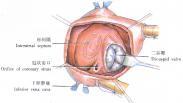

伤寒是伤寒杆菌引起的。主要的病理特征是全身网状内皮系统的增生反应,以回肠下段淋巴组织的病变最为显著。副伤寒,分别由副伤寒甲,乙,丙杆菌引起。它的临床表现、诊断、治疗和预防与伤寒相同。